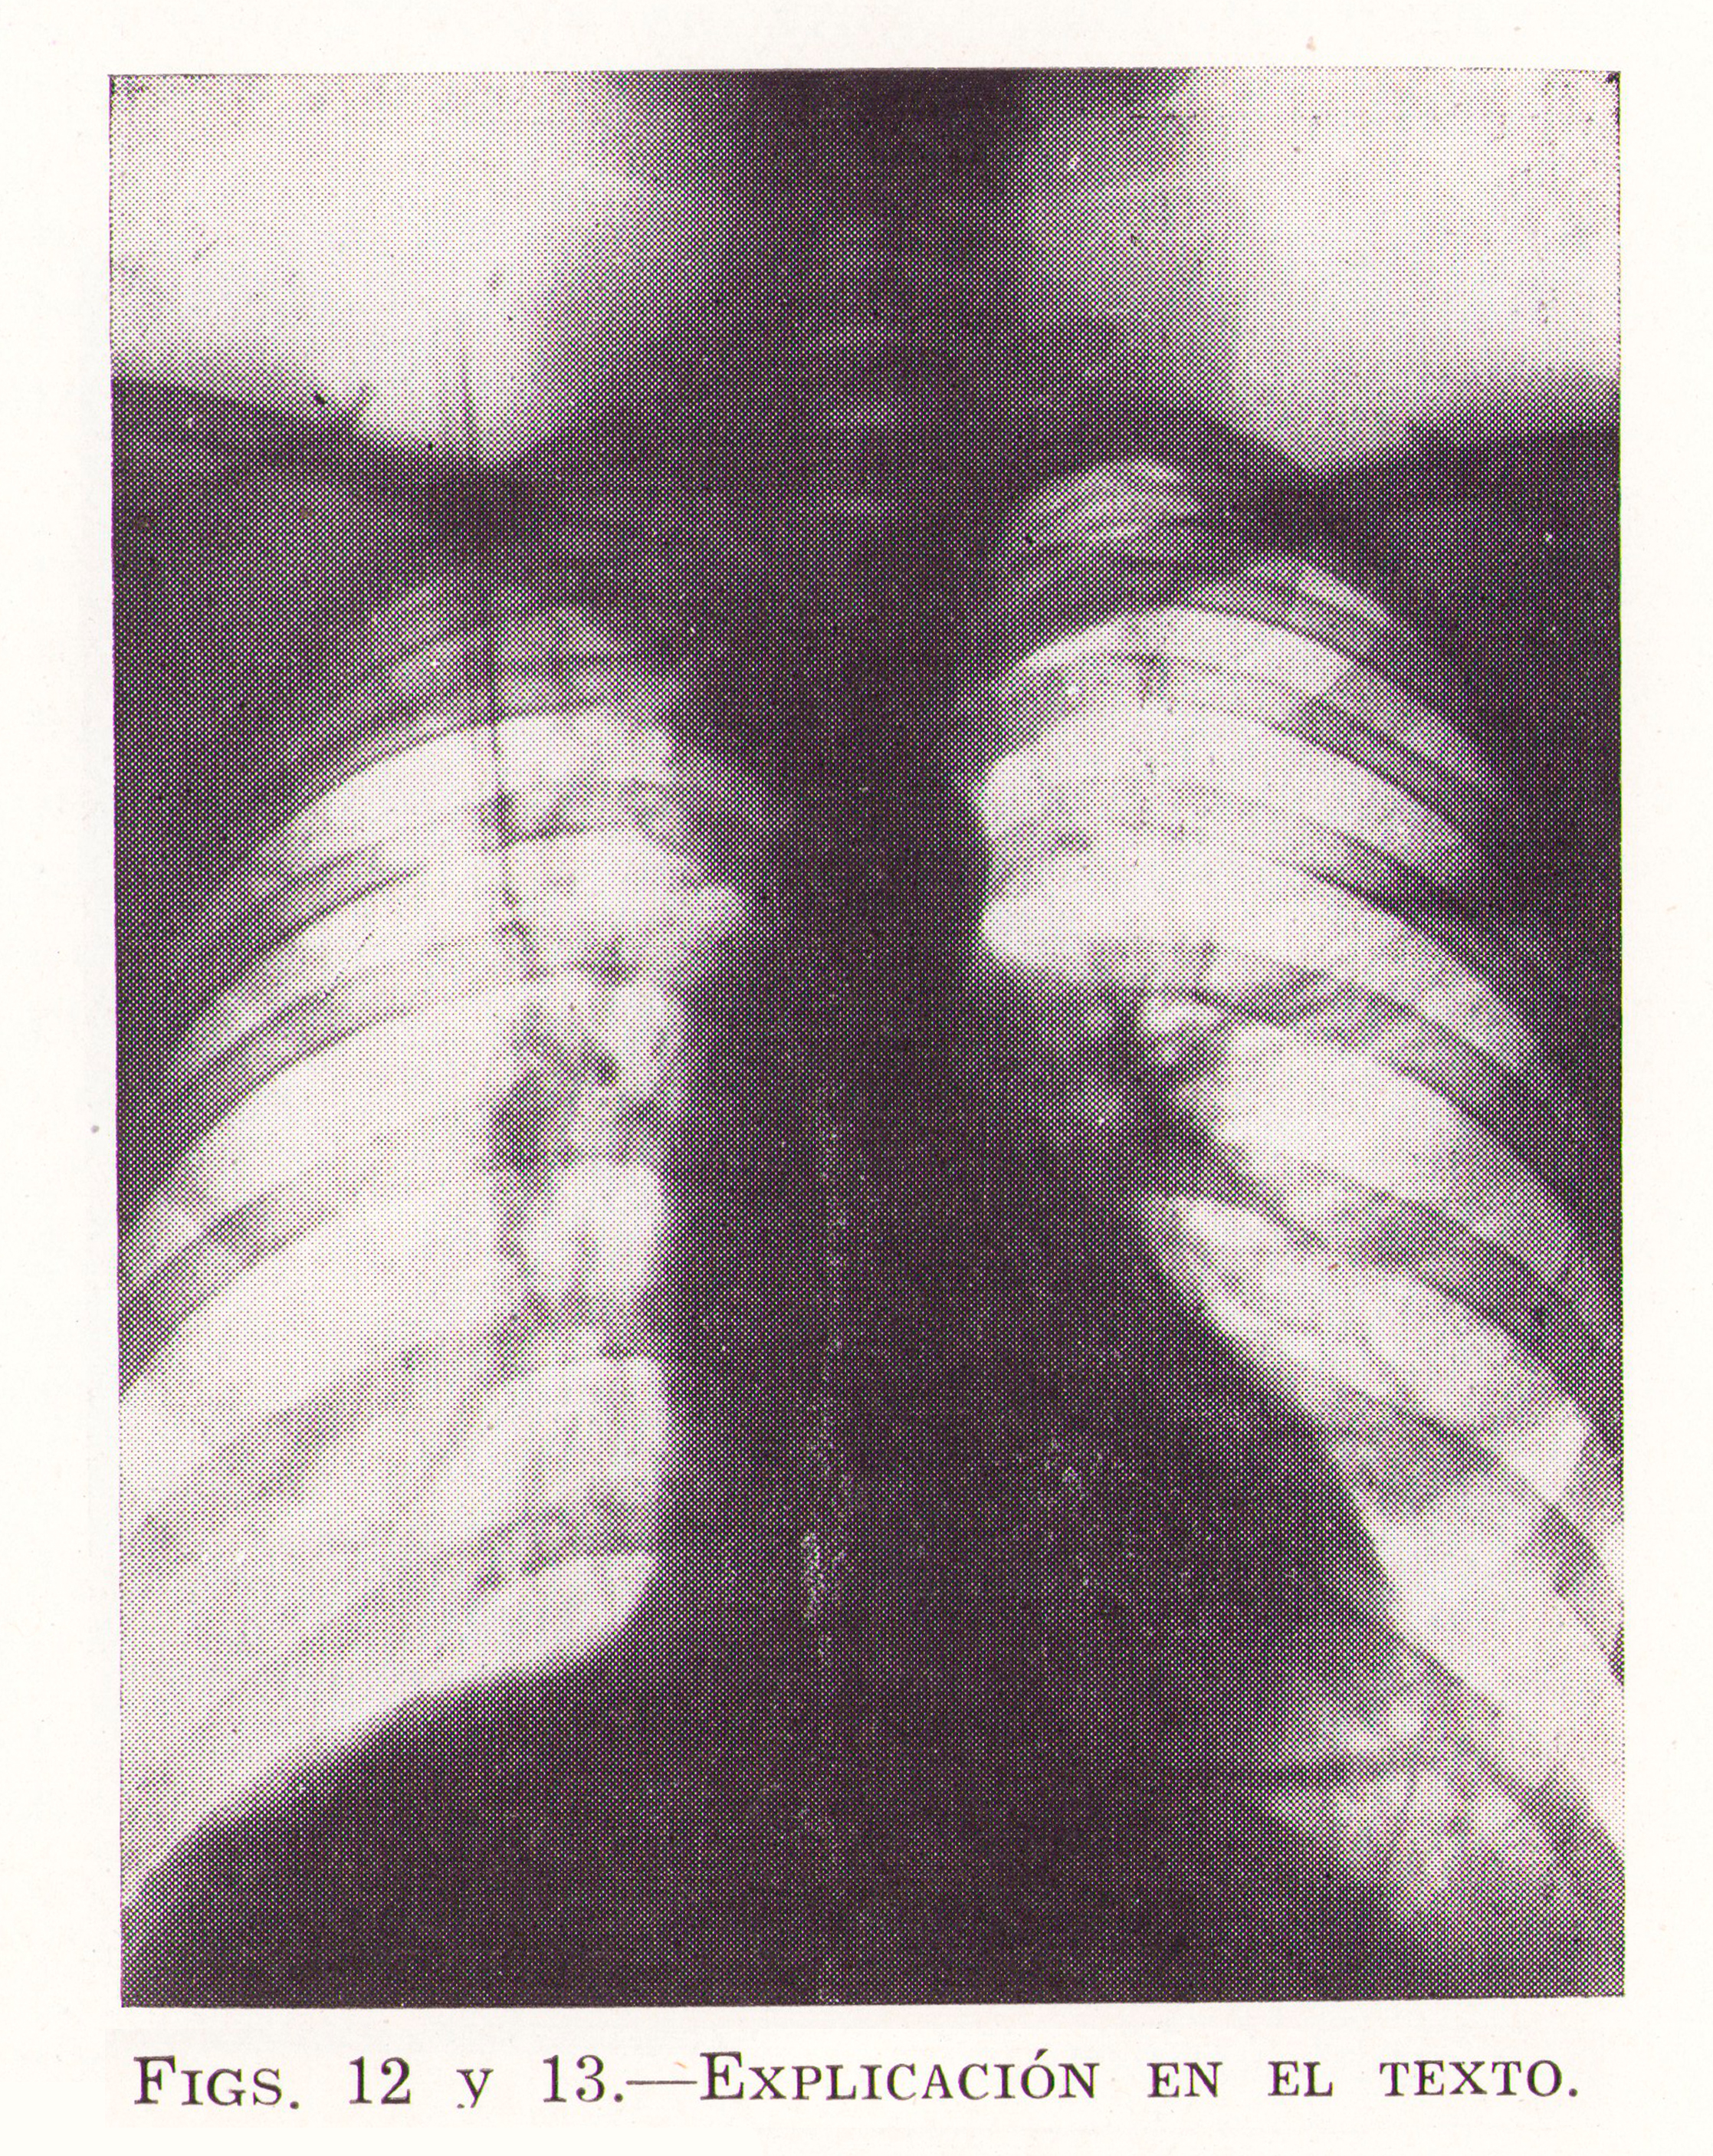

Fig.13. Revista Española de ciencias médicas, Clínica y laboratorio, 1953.